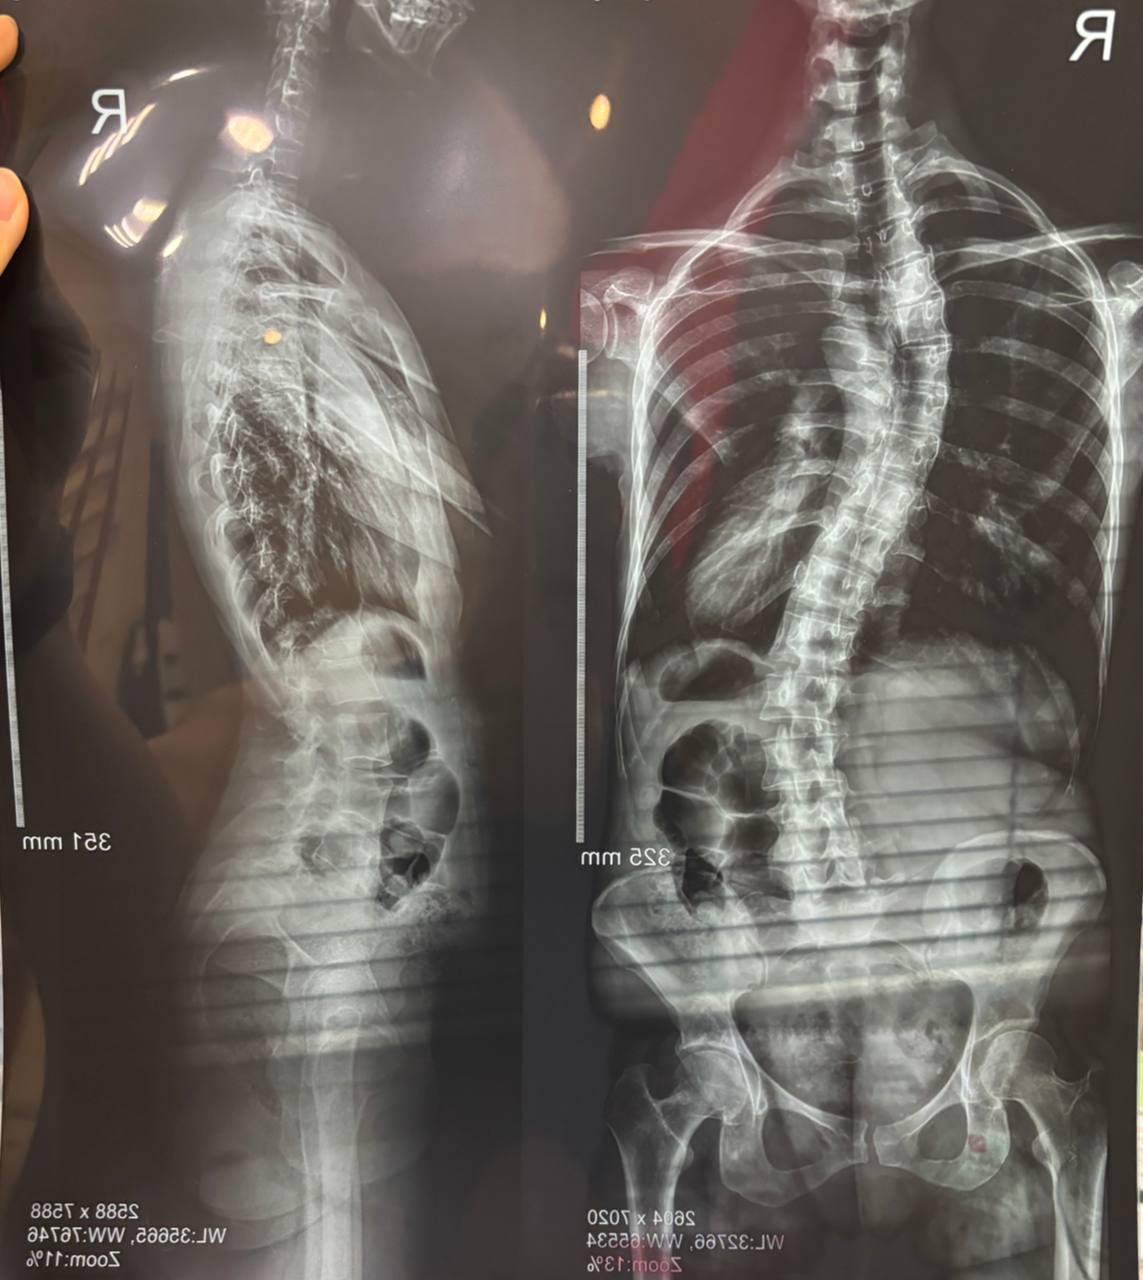

1️⃣Нам нужна полная картина и понимание что происходит с костными структурами внутри тела, как выглядят дуги сколиоза, ребра и тазовые кости.

2️⃣Мы измеряем или проверяем углы Кобба( величина сколиотической дуги) и оцениваем форму позвонков.

3️⃣Проводим дополнительные измерения фронтального баланса и саггитального профиля уже ориентируясь на тела позвонков.

4️⃣Оцениваем степень зрелости опорно-двигательного аппарата тестом Риссера. Это помогает понять риск прогрессии сколиоза.

Рентгенологическое исследование позвоночника помогает специалисту сделать полноценную объективную оценку вашего сколиоза. Поэтому мы просим делать именно постуральный снимок, где видно сразу весь позвоночный столб с захватом костей таза.